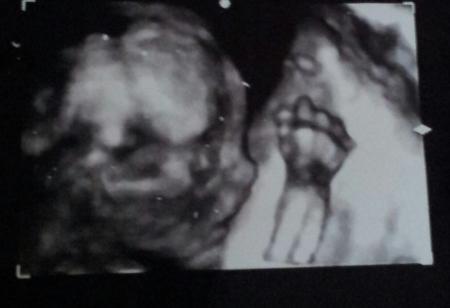

Bekam um 14Uhr einen Anruf das wir bitte um 15:30Uhr schon kommen sollen, Frau Dr. muss später zu einer Geburt. Gesagt getan, ab zum Arzt. Sie hat super lange geschallt, dem Zwerg geht es bestens, alles dran und so wie es sein soll. Stolze 21cm von Kopf bis Fuß und 290g schwer. Das aller beste aber, ich hab ein schönes 3D Profil Bild bekommen und sie ist sich ziemlich sicher das es ein kleines Mädchen wird, ich bin total happy. LG Steffi mit Mia-Sophie an der Hand und Romy-Marie im Bauch

Sie sieht genau wie mia

Hallo aus dem Dezember-Bus Ich bin stille Mitleserin, aber jetzt muss ich einfach was schreiben: Das ist Bild ist einfach traumhaft! Dein Baby sieht so süß aus! LG Nicole